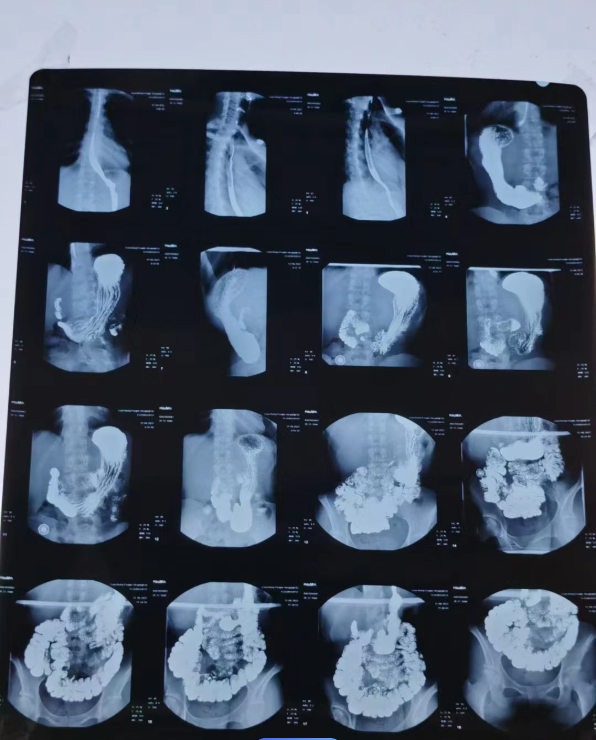

Medical industry: Barium compounds are also widely used in the medical industry. Barium meals (such as barium tablets) are used in gastrointestinal X-ray examinations to help doctors observe the functioning of the digestive system. Barium compounds are also used in some radioactive therapies, such as radioactive iodine for the treatment of thyroid disease.